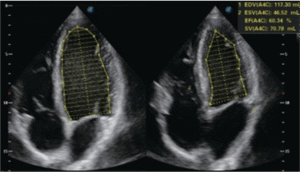

Echocardiography remains one of the gold standards for diagnosing and monitoring heart disease, including cardiomyopathies, valvular disease, and pericardial effusion.

→ Echocardiography to assess cardiac structure and function before initiating treatment

• Cardiology